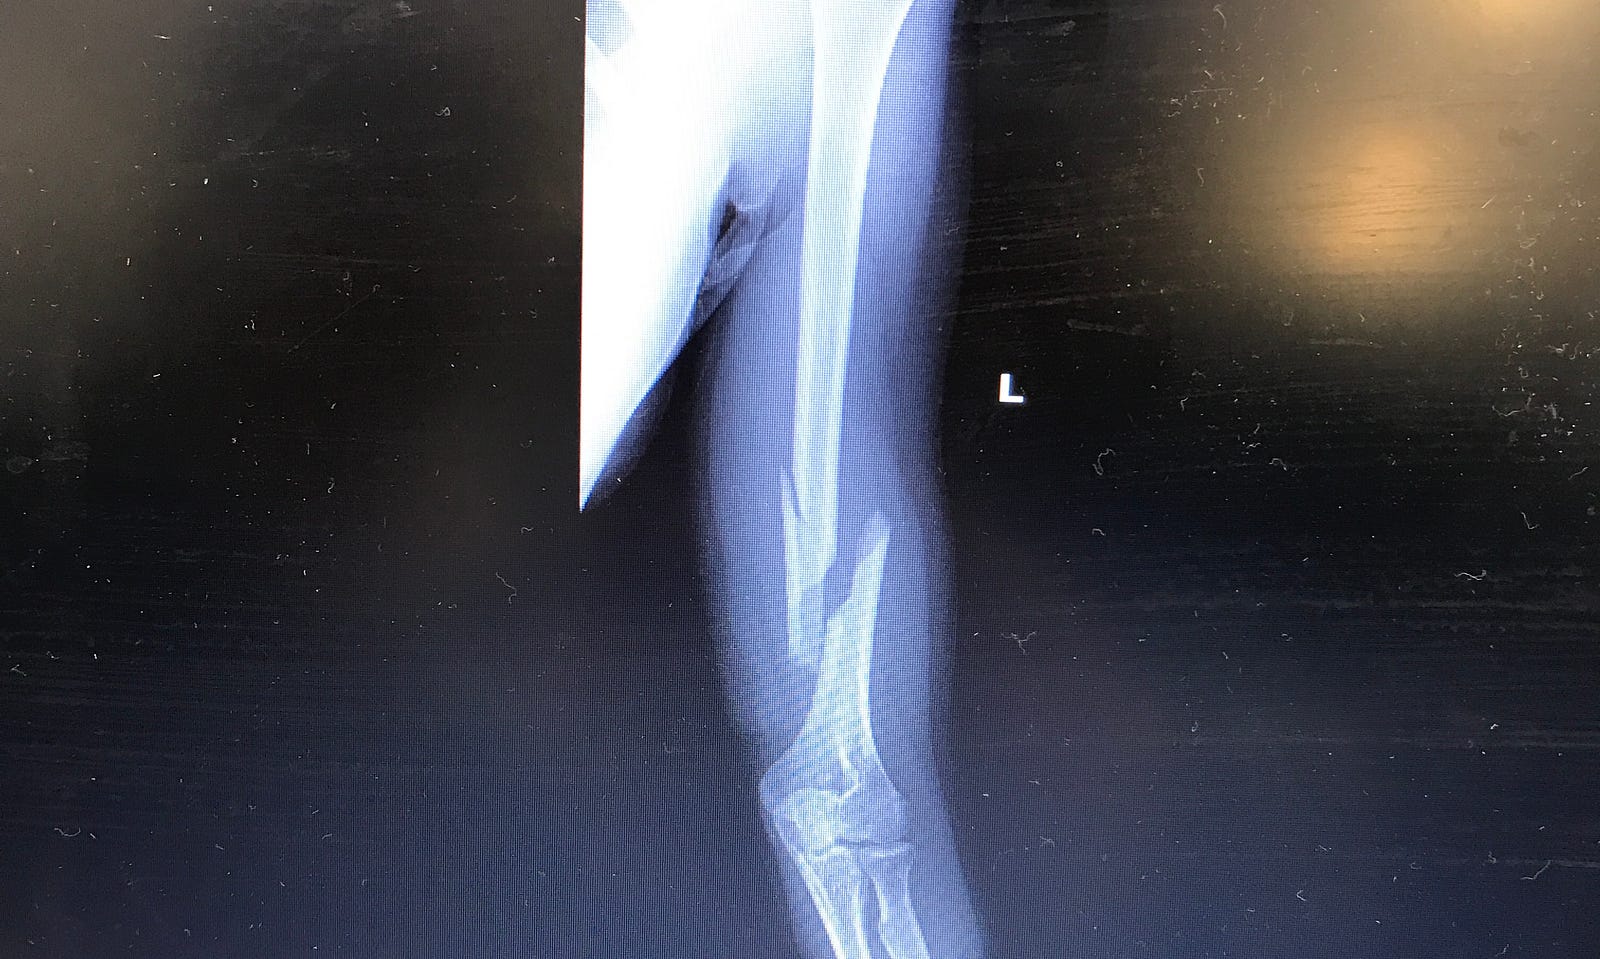

A Broken Humerus — Road to Recovery Maddie Wirthman Medium How To Shower With A Broken Humerus I recently fractured my left humerus and found that reading humerus fracture recovery blogs has been helpful in anticipating the healing process. There are two main approaches that your surgeon may use: During the first four weeks it is. In this video the surgeons discuss shoulder fractures. Shampoo and conditioner in basket at. They discuss the mechanism of injury, the.. How To Shower With A Broken Humerus.

A Broken Humerus — Road to Recovery by Maddie Wirthman Medium How To Shower With A Broken Humerus Wear the sling all the time, only removing it to regularly exercise your arm, and to shower. They discuss the mechanism of injury, the. Try to do this every 1 to 2 hours for the. Shampoo and conditioner in basket at. During the first four weeks it is. In this video the surgeons discuss shoulder fractures. If you have an. How To Shower With A Broken Humerus.